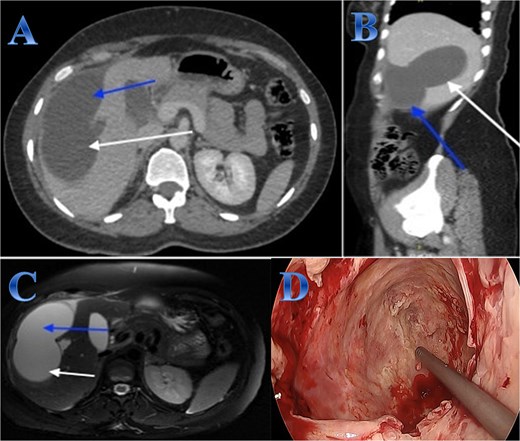

A 42-year-old woman experiences 3 weeks of right upper quadrant pain. On examination showed mild epigastric enlargement and tenderness. Laboratory tests showed eosinophilia, increases in total and direct bilirubin levels. The US discovered a large heterogenous mass with minimal expansion of IHBRs. Abdominal CT revealed large calcified right hepatic lobe cyst with dilated IHBRs (Fig. 1).

Case 1. (A & B) Sagittal and coronal CT cuts of the abdomen at venous phase showing a large peripherally calcified heterogeneous hypodense mass in the right hepatic lobe (photo A), with internal septations and small cysts (daughter cysts), with dilated IHBRs (photo B). (C & D) Coronal MRI images of the abdomen (follow up study) showing biliary extension of the lesion, CBD and the hepatic duct and sub hepatic fluid signal.

A preoperative Albendazole of 400 mg twice daily was started for 8 weeks. An ERCP paired with sphincterotomy, and stenting of the biliary ducts revealed a gelatinous substance with many daughter cysts that came through the ampulla of Vater. The severity of the lesions required an open surgical approach as it is a sizeable CE communicating with common and right hepatic ducts, treated by total peri-cystectomy and closure of the communication with common hepatic duct (CHD) and right hepatic duct (RHD). The cyst was isolated using gauze pads soaked in hypertonic saline. The cyst was punctured with a needle, and its contents were aspirated to reduce intra-cystic pressure. The gall bladder was adherent to the cyst, so cholecystectomy was done; after that, through the cystic duct, contrast material was injected, and it came through two intraparenchymal openings. These two intra-parenchymal openings were closed through deep sutures in two layers. A cholangiogram was done to make sure there was no stenosis or leakage (Fig. 1).